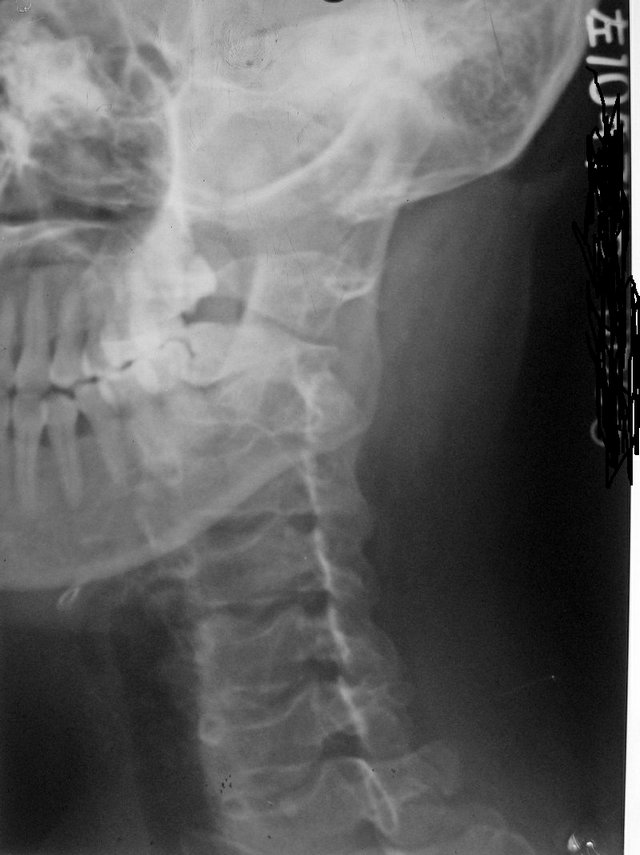

以下是引用拾荒者在2010-7-5 21:08:00的发言:[br]1.膝关节退行性变;2.颈椎未见明显异常。

以下是引用hexue在2010-7-5 22:47:00的发言:[br]1.膝关节退行性变;2.颈椎未见明显异常。 [br] [br]

以下是引用随光逐影在2010-7-6 7:11:00的发言:[br]病例1:双膝关节退行性骨关节病。[br]病例2:1)颈椎未见明确异常。2)一侧下颌智齿横位阻生。